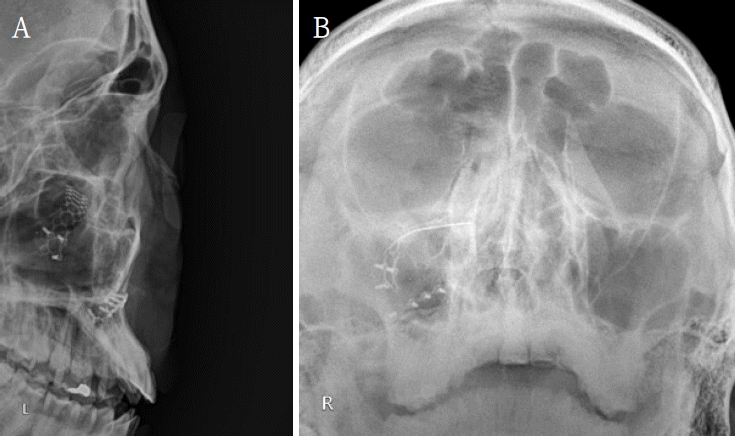

A 19-year-old male presented to the Emergency Department of Chonnam National University Hospital after sustaining facial trauma from slipping on the stairs. Severe swelling involving the left periorbital region and an approximately 2.0 cm laceration wound were observed on the left lower lip. The patient’s vital signs were stable, and neurological function was intact.Clinical examination revealed normal ocular motility, intact infraorbital sensation, and well-maintained globe position without diplopia or enophthalmos.A maxillofacial CT scan was performed for further evaluation. CT imaging demonstrated fractures of the left medial orbital wall, inferior orbital wall, and nasal bone (Fig. 1). The medial wall defect was located adjacent to the ethmoid sinus with partial herniation of orbital soft tissue. The inferior orbital wall fracture extended posteriorly with minimal displacement of the bony fragments, and a depressed nasal bone fracture was also confirmed.Initial management included primary closure of the lower-lip laceration under local anesthesia. Reduction of the orbital and nasal bone fractures was performed under general anesthesia using a multidisciplinary approach involving the Departments of Otorhinolaryngology and Oral and Maxillofacial Surgery.First, the medial orbital wall was repaired by the otorhinolaryngology team using an endoscopic transnasal approach with a navigation system (Fiagon Navigation System, Fiagon GmbH, Hennigsdorf, Germany). After uncinectomy and anterior ethmoidectomy, additional posterior ethmoidectomy was performed, followed by widening of the frontal and sphenoid ostia. This provided a clear surgical field for orbital compression and visualization of the left medial orbital wall fracture site (Fig. 2). The medial wall showed diffuse destruction with generalized herniation of the periorbita. After careful reduction of the herniated contents, a customized silastic sheet was inserted in an inverted U-shape (Fig. 3).Subsequently, the oral and maxillofacial surgery team performed intraoral access for reconstruction of the orbital floor. A vestibular incision approximately 3 cm in length was made, extending from the left canine to the first molar region. A bony window measuring approximately 15 × 10 mm was created in the anterior wall of the maxillary sinus to provide direct visualization of the inferior orbital wall defect. Herniated orbital tissue was carefully repositioned into the orbital cavity, and the orbital floor was anatomically reconstructed. A titanium miniplate with screws (DePuy Synthes, Oberdorf, Switzerland) was applied across the fracture line to achieve rigid fixation (Fig. 4). Layered closure was then performed to ensure proper wound healing and anatomical restoration.Finally, closed reduction of the nasal bone fracture was performed to restore nasal contour and symmetry. To maintain medial wall reduction and provide uniform compression, Merocel® (Medtronic Xomed, Jacksonville, FL, USA) was inserted into the ethmoid cavity. The operation proceeded smoothly without intraoperative bleeding, orbital content injury, or infraorbital nerve disturbance, indicating stable surgical control.Immediate postoperative CT confirmed successful reduction of both fractures. The patient experienced complete resolution of diplopia and ocular discomfort, while infraorbital sensation remained mildly decreased but improving. At two weeks, Merocel® packing was removed, and routine dressing was performed. At two months, follow-up CT and endoscopic examination demonstrated stable reconstruction, and the silastic sheet was removed (Figs. 5 and 6). The patient’s sensation had nearly recovered, and postoperative outcomes remained stable with preserved ocular movement, normal globe position, and proper occlusion.

Figure 6.

Postoperative radiographs show stable fixation and orbital symmetry. A. Lateral skull radiograph shows intact titanium miniplate fixation of the left orbital floor without displacement. B. Waters’ radiograph demonstrates symmetric orbital outline and stable reconstruction compared with the contralateral side.